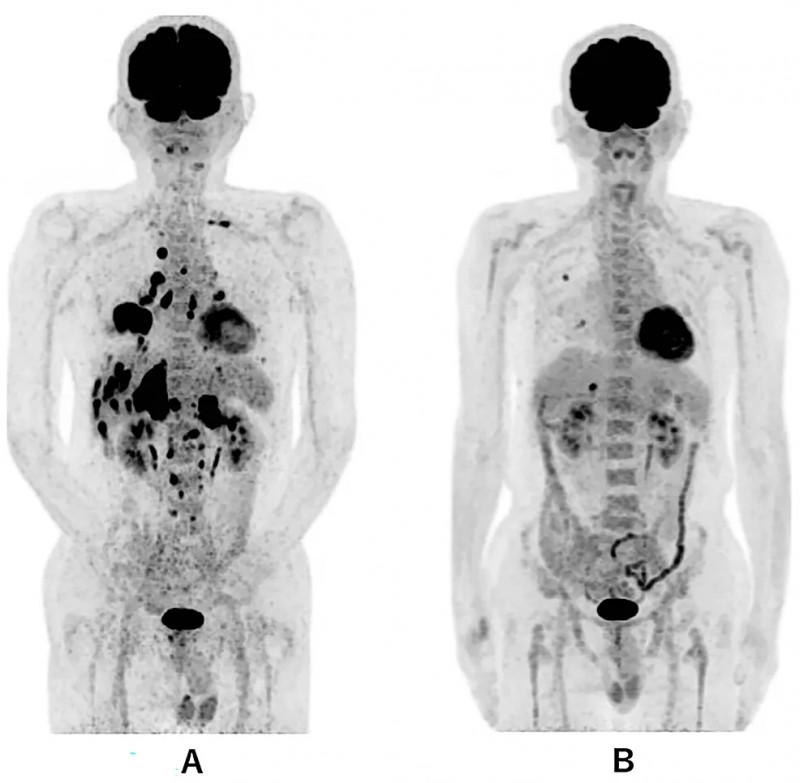

《Cureus》期刊报道了一个40岁晚期小肠癌男性患者的救治案例:该患者合并主动脉旁淋巴结转移与腹膜播散,对化疗无应答,且出现胆管、十二指肠梗阻,已接受胆管支架置入及中心静脉营养支持。因腹部癌痛剧烈,患者先接受8Gy单次姑息性调强放射治疗(IMRT),但疼痛控制不佳,体能状态(PS)评分为4分,需依赖轮椅活动。随后患者入组创新联合治疗方案:IMRT放疗3周后,启动WT1-DC疫苗+α-半乳糖神经酰胺脉冲树突状细胞(α-Galcer-DC)+纳武单抗输注治疗,同时配合两次活化淋巴细胞治疗,总疗程约3个月。

治疗效果显著:治疗前后3个月的腹部CT显示小肠癌病灶大幅减少(详见下图);血液检查提示CA19-9肿瘤标志物水平显著下降,胆红素降低,肝功能明显改善。更令人振奋的是,患者腹痛缓解,恢复流质饮食,PS评分提升至2分——无需拐杖即可步行至医院,且能自主完成如厕、洗澡等日常活动。

该案例证实,放疗与树突状细胞疫苗的联合方案可有效抑制癌症进展,为化疗无应答的晚期患者带来生存希望。尤其值得关注的是,WT1-DC与α-Galcer-DC的双疫苗组合,其协同激发的抗肿瘤免疫效应或优于单一疗法,为晚期癌症的免疫联合治疗带来了新的选择!

▼该患者接受DC免疫治疗前与治疗后的肿瘤大小对比

▲图源“Cureus”,版权归作者所有,如无意中侵犯了知识产权,请联系我们删除